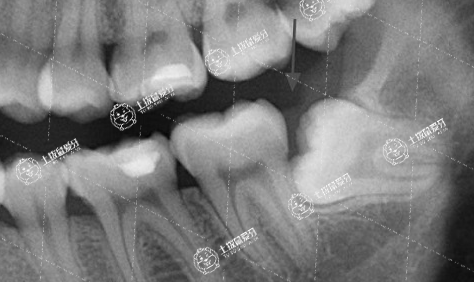

在這里小編可以肯定的告訴大家,牙齒矯正過程中智齒不一定要拔掉,需要醫(yī)生根據(jù)你智齒的生長情況來判斷的,一般不主張拔除正常的智齒,但是,有4種情況是例外的。

1、因矯正需要通過拔除智齒,獲得足夠的空間把牙齒后推移動的,或會影響治療效果的,這是非拔不可的。

智齒不正常萌出

2、對口腔健康有影響,比如把前面的牙齒頂壞了,或者歪著長或斜著長了,造成食物殘?jiān)菀浊度?,這種情況也建議把智齒拔除。

3、智齒的位置總是發(fā)炎、牙齦紅腫,即使是不正畸,也可以把它拔掉了。

4、智齒本身健康狀況不好,蛀牙嚴(yán)重,沒有保留價值的,也需要拔除。